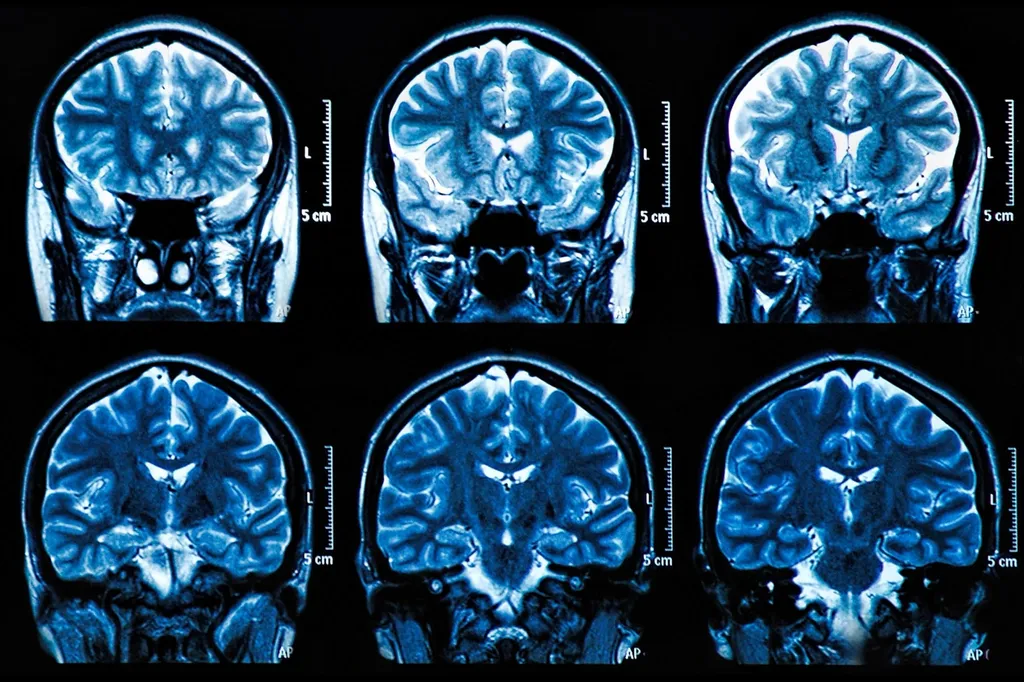

MRI Brain Scan Neuroscience Images

“目前,診斷阿爾茨海默病需要神經成像,”皮特大學精神病學助理教授、資深作者Thomas Karikari博士說。“這些檢查很昂貴,需要很長時間來安排,即使在美國,許多患者也無法使用核磁共振成像和PET掃描儀。可訪問性是一個主要問題。”